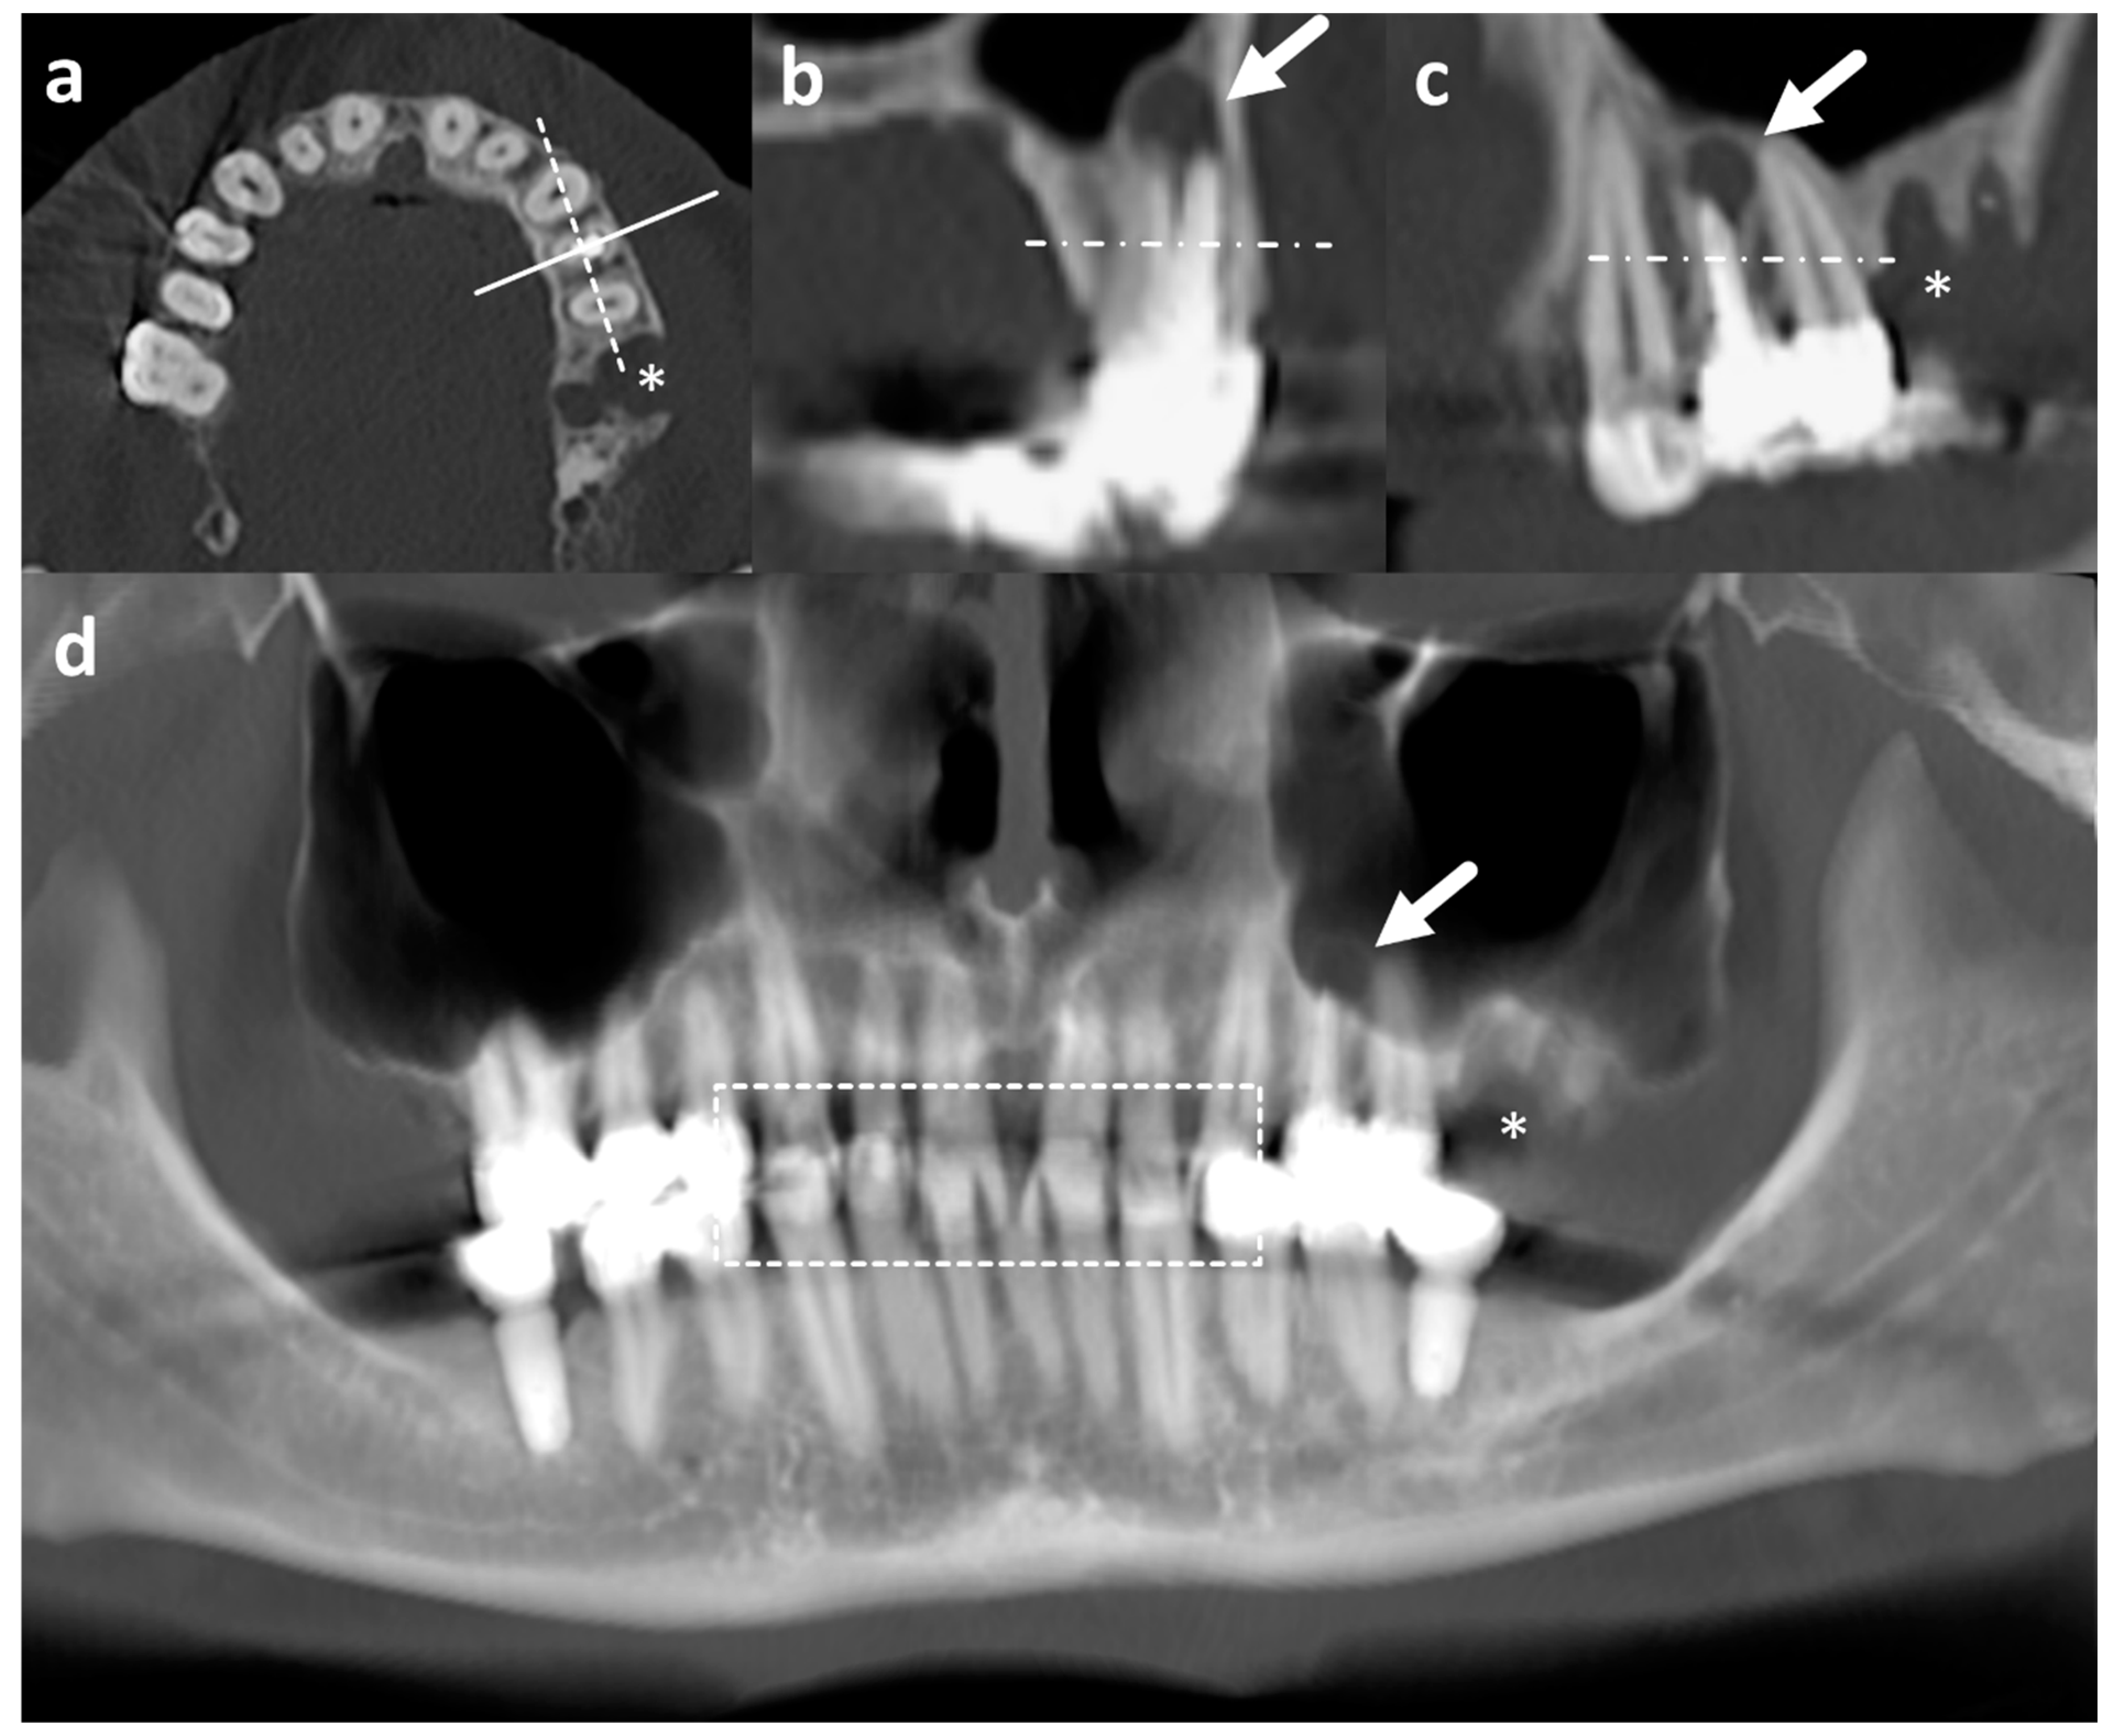

2.2. Image Acquisition, Reconstruction, and Radiographic Assessment

2.2.1. CT

2.2.2. Virtual Orthopantomogram (vOPG)

2.2.3. Radiological Evaluation

2.2.4. Assessability